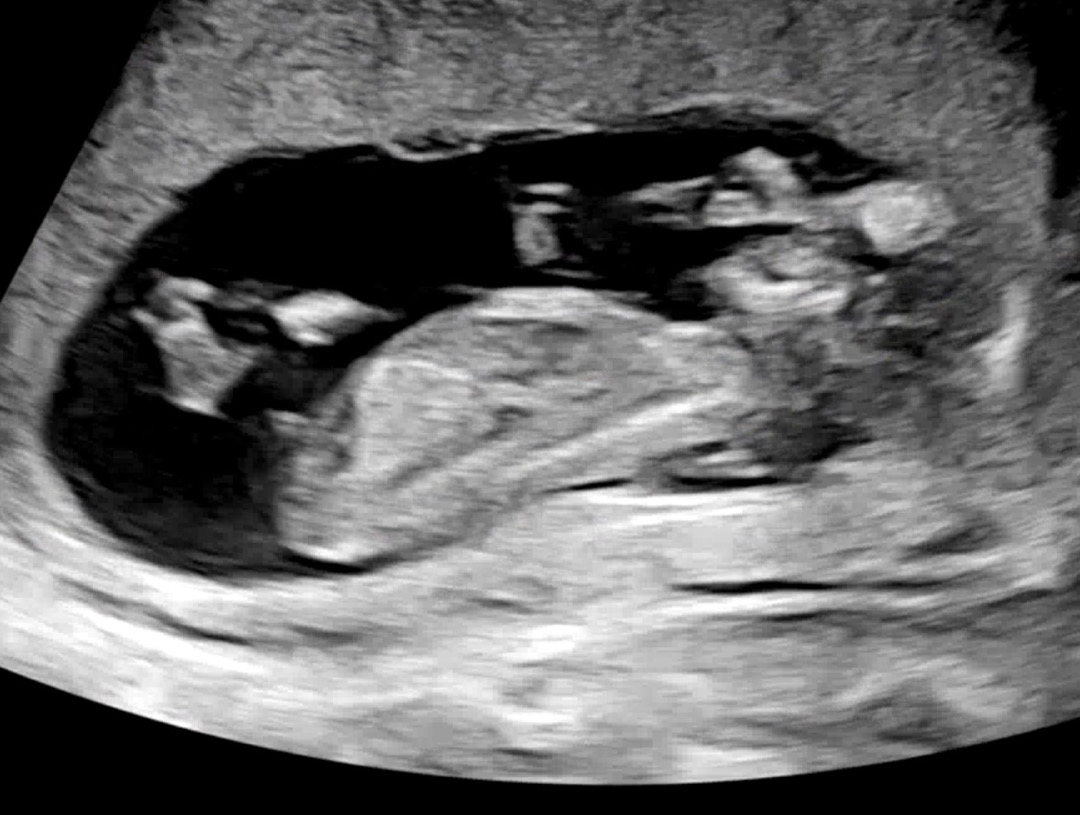

12주 4일 각도법 한 번만 봐주세요!!

각도법 한 번 투표해주세요!